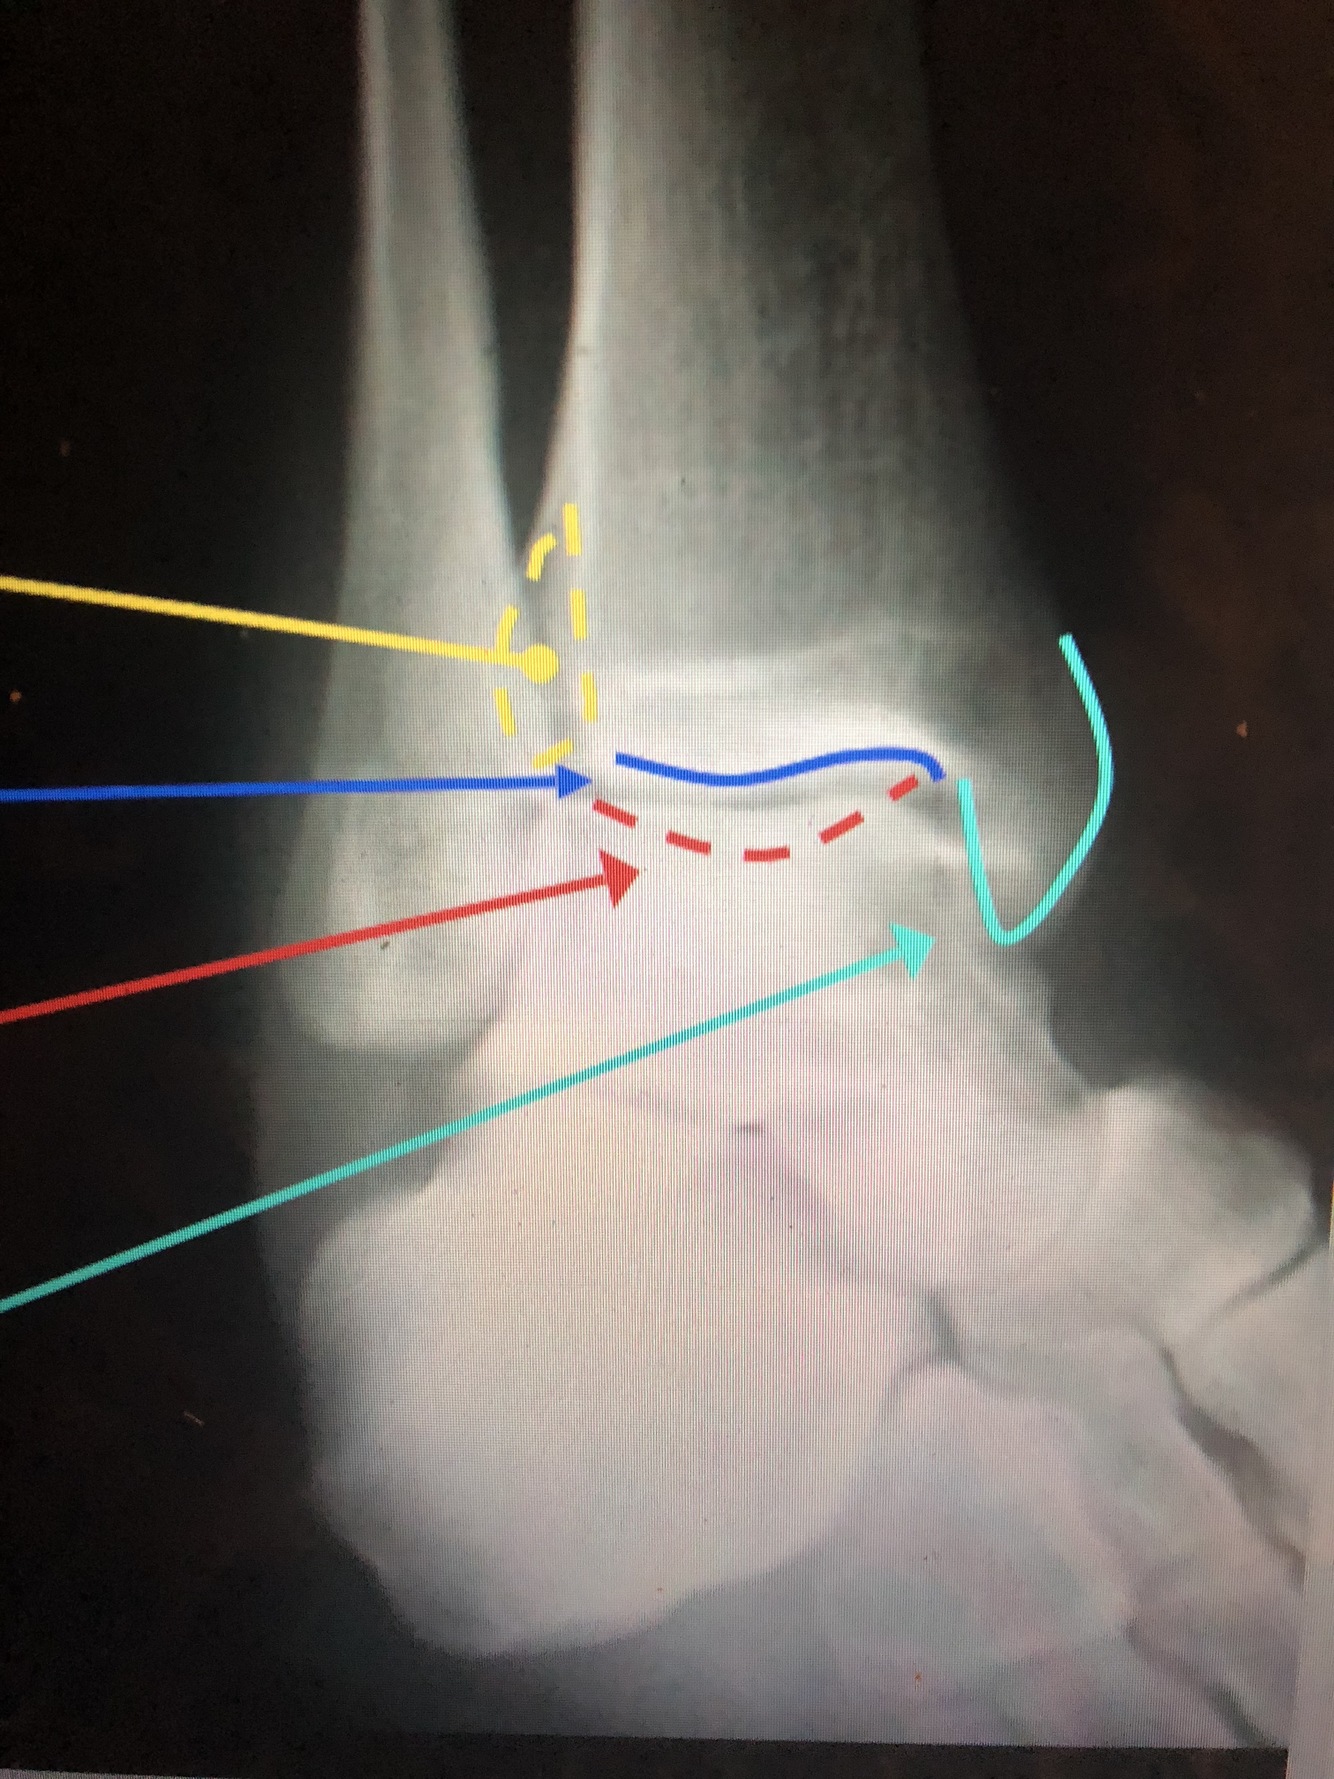

What is the dark blue line?

Lateral margin of the Tibia

What is the red line?

Plafond

What is the light blue line?

Medial Malleolus

What is the yellow dotted line?

Fibular Notch

Posterior Malleolus